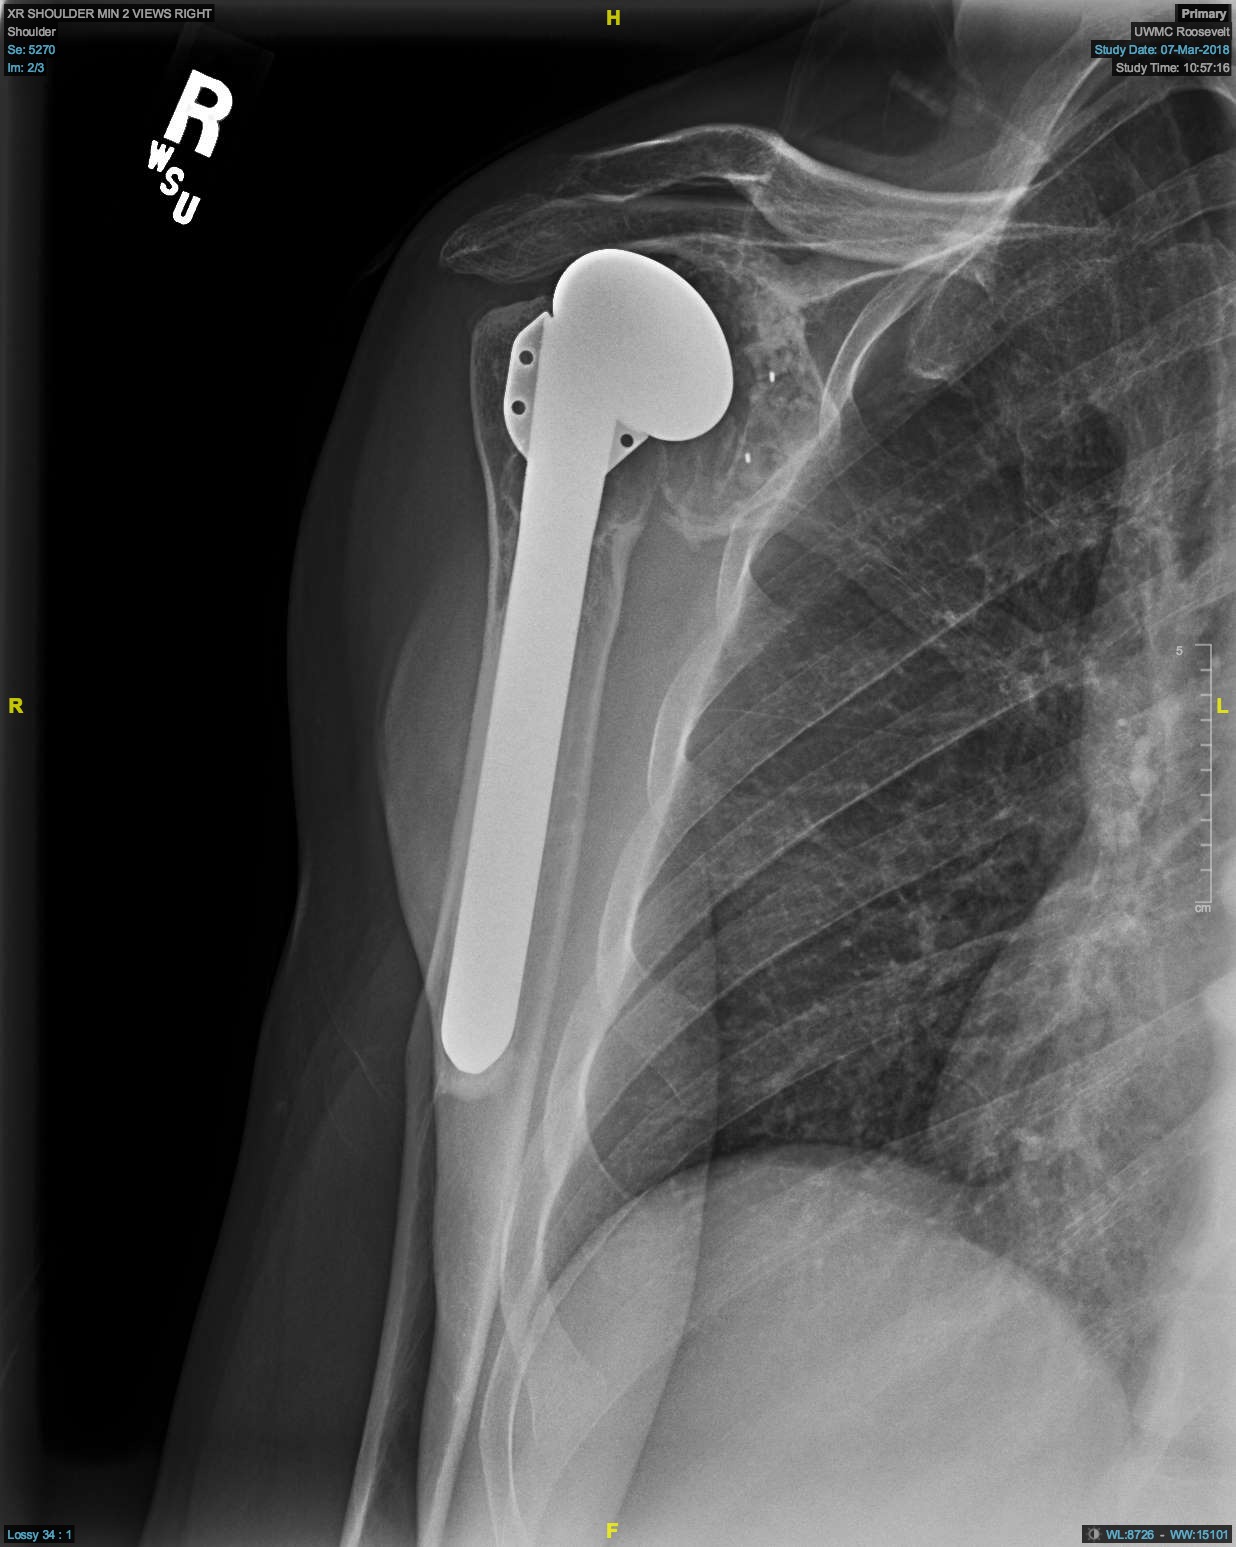

Shoulder Joint Replacement OrthoInfo AAOS How Long Does A Shoulder Replacement Hurt After shoulder surgery, you may have pain from the surgery and pain. Knowing what to expect after shoulder replacement can help you. full recovery from shoulder replacement can take 4 to 6 months or longer. surgery aims to: Improve range of motion and mobility. Experts estimate that most modern shoulder replacements will last for. it’s difficult to. How Long Does A Shoulder Replacement Hurt.

Shoulder Replacement Reno, Sparks, Carson City ROC How Long Does A Shoulder Replacement Hurt full recovery from shoulder replacement can take 4 to 6 months or longer. surgery aims to: After shoulder surgery, you may have pain from the surgery and pain. depending on the type of shoulder surgery and amount of repair work involved, pain may be expected for weeks or even months following the. Improve range of motion and. How Long Does A Shoulder Replacement Hurt.

Partial or Total Shoulder Replacement Dr Skedros Orthopaedics How Long Does A Shoulder Replacement Hurt full recovery from shoulder replacement can take 4 to 6 months or longer. it’s difficult to say just how long your shoulder replacement will last. Experts estimate that most modern shoulder replacements will last for. surgery aims to: The surgery may not fully. although rare, it's possible that shoulder replacement surgery won't lessen your pain or. How Long Does A Shoulder Replacement Hurt.